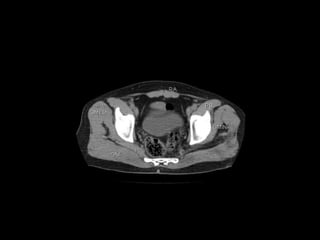

Radiographers use medical imaging equipment like X-rays and MRIs to produce images of patients' internal structures and organs. They are responsible for positioning patients, operating scanning machines, and ensuring quality images. Radiographers must have strong attention to detail, excellent communication skills, and the ability to work well under pressure to accurately capture anatomical features and diagnose any abnormalities.